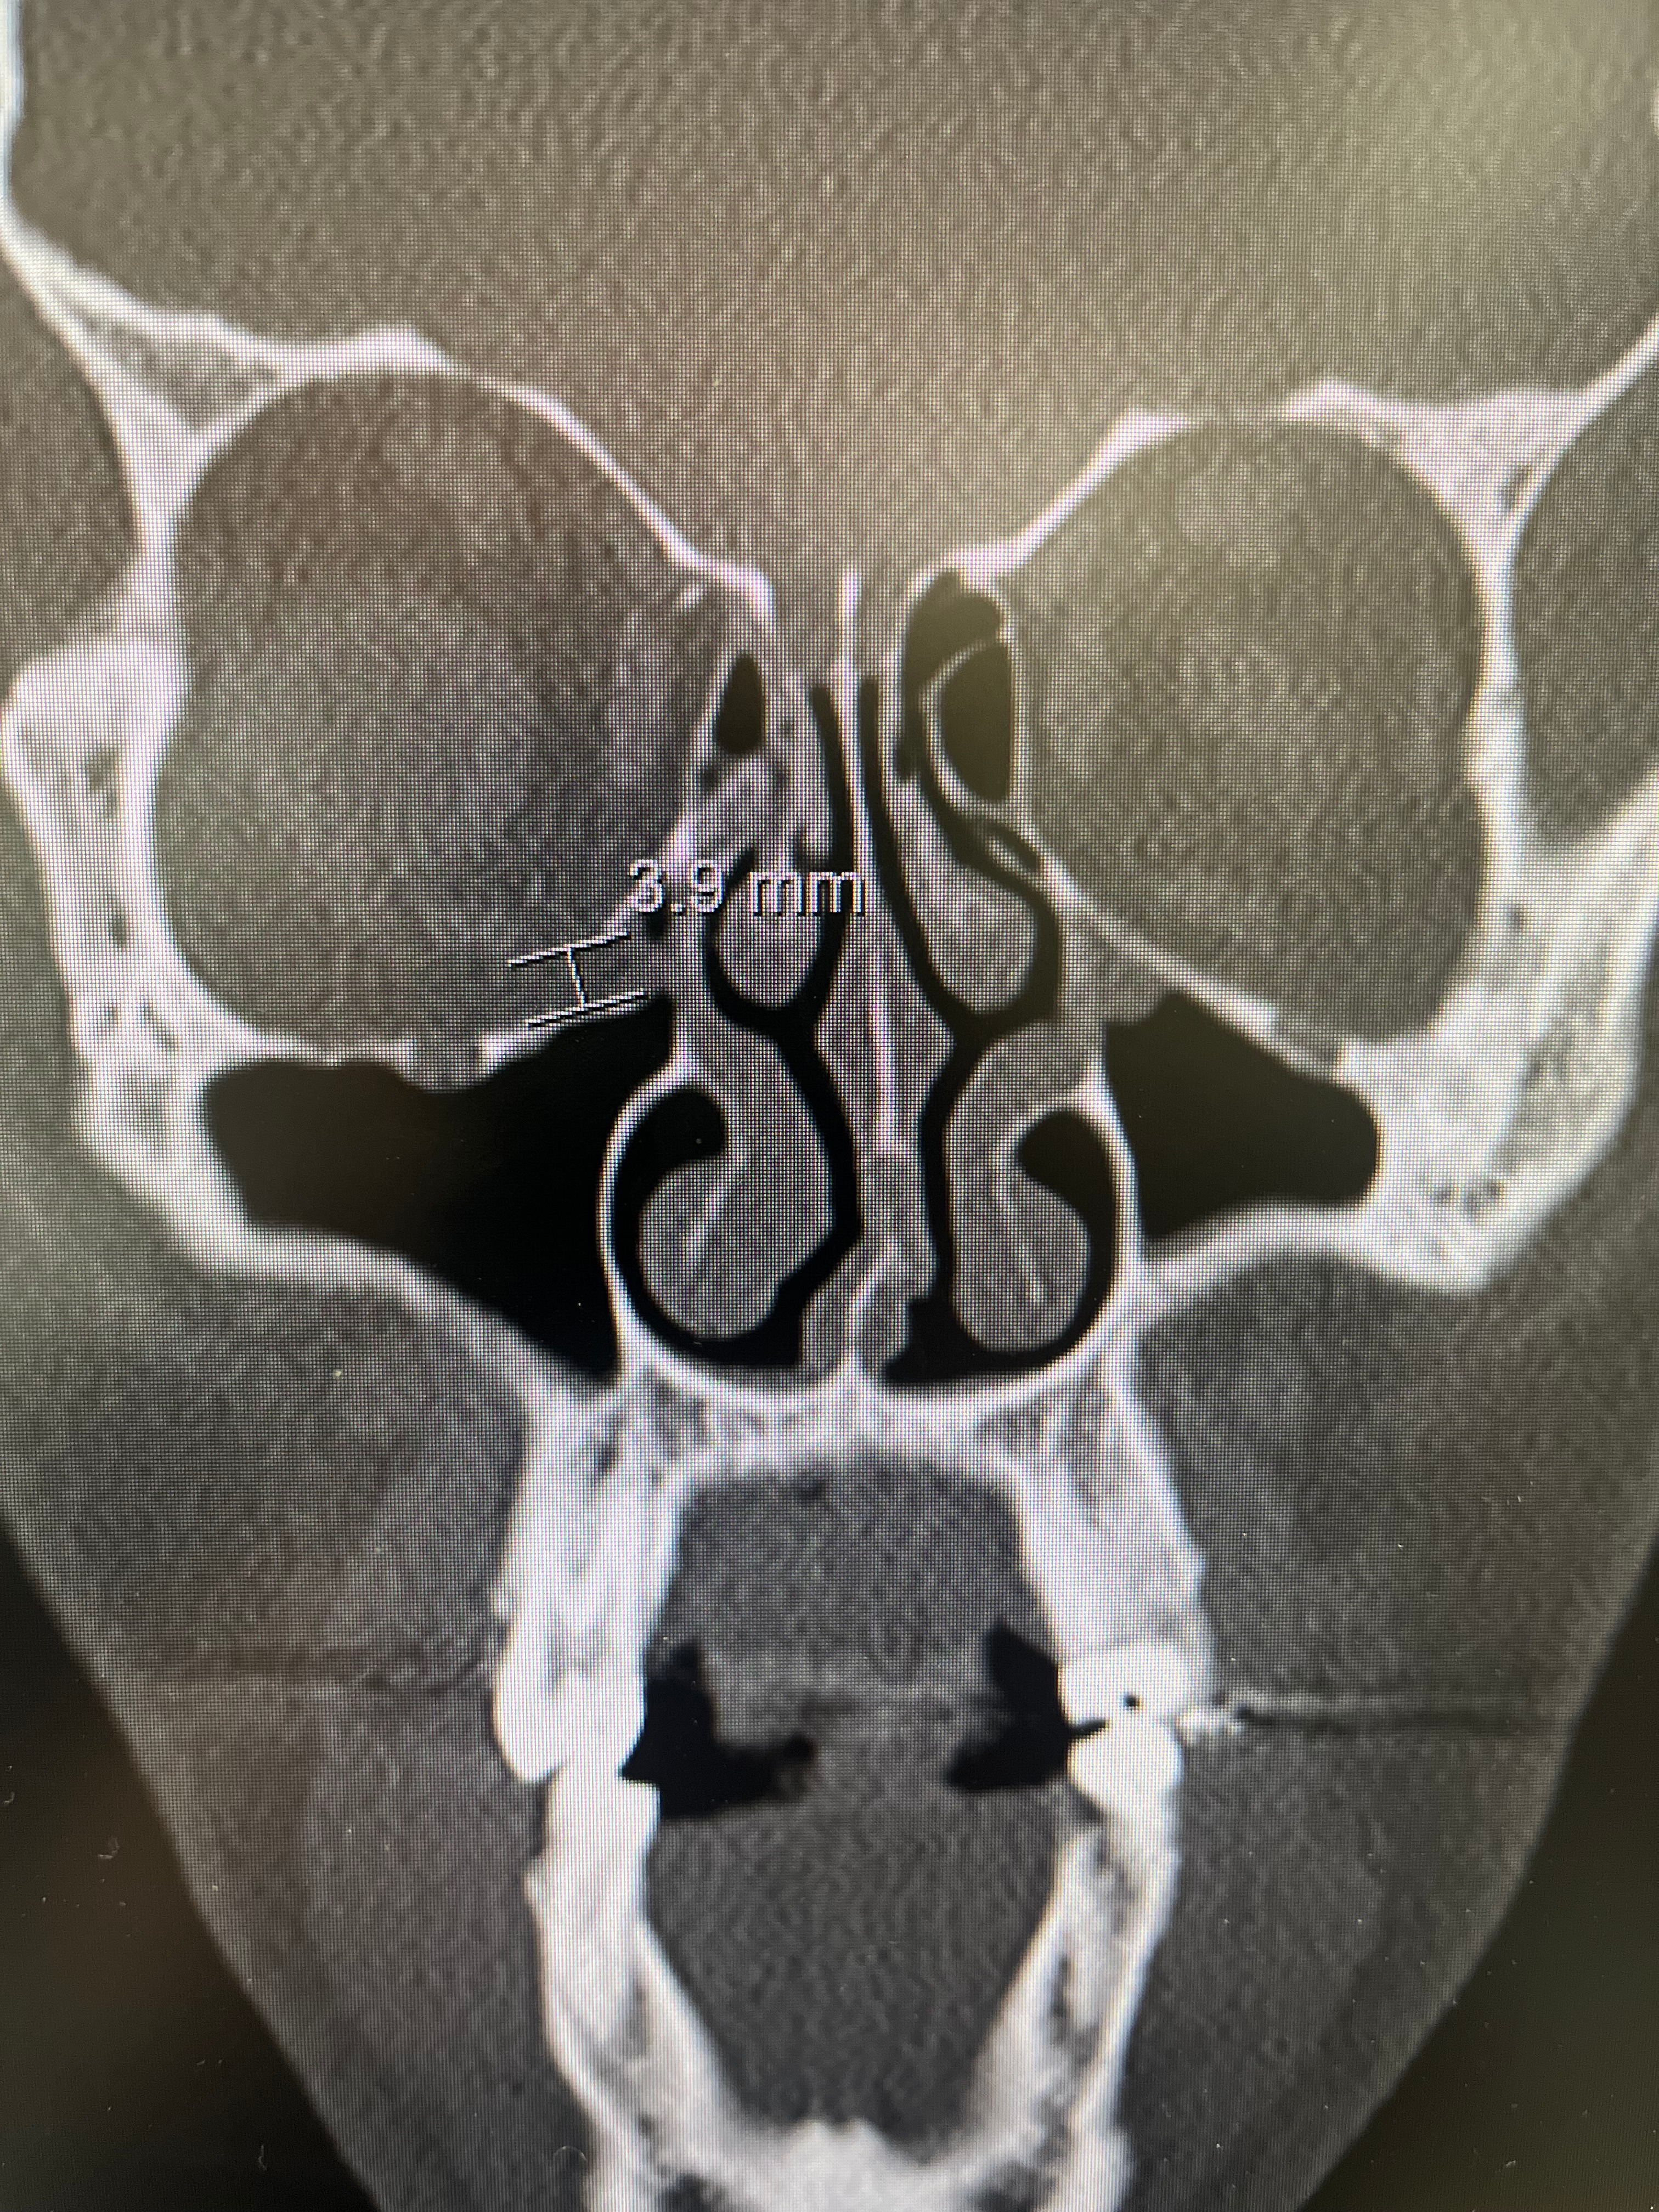

We're reaching out to rally support for our assistant baseball coach, Matt Thomas, who recently suffered a serious injury while doing what he loves—coaching young athletes. While working in the batting cages, and at no fault of his own, Coach Matt was struck in the eye by a baseball, resulting in an orbital floor blowout fracture that requires urgent surgery (a fracture to his eye socket). He also suffered a fracture to his nose that may require surgery.